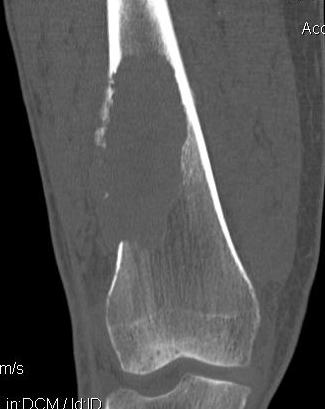

Tibia

Greenbaum et al Am J Orthop 2017

- 43 tibial metastasis

- proximal tibia most common

- variety of treatements

- plate / nail / arthroplasty